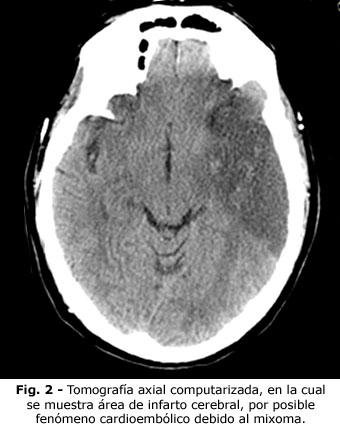

Se realizó el diagnóstico de infarto cerebral del hemisferio derecho, confirmado mediante TAC (tomografía axial computadorizada) y se ingresó con tratamiento y rehabilitación precoz, según el protocolo establecido.

Se le realizaron estudios hemodinámicos, la coronariografía fue normal, sin lesión valvular mitral. Se extirpó un tumor de gran tamaño. En anatomía patología se comprobó que se trataba de un tumor benigno, muy friable: mixoma con pedículo largo, que le permitía permanecer en el ventrículo izquierdo y enclavado en el orificio valvular mitral. Después de la intervención, el enfermo ha evolucionado bien, con seguimiento en consulta de cardiología y tratamiento para su hipertensión (ver Fig. 1, Fig. 2 y Fig. 3).

El tumor cardiaco primario más frecuente, es el mixoma, cuando es grande, suele ser friable, de gran movilidad y da lugar a fenómenos cardioembólicos, tanto pulmonares (cuando son derechos) y sistémicos (cuando son de cavidades izquierdas).(8,9) Cuando se diagnostica un infarto cerebral, es preciso tener en cuenta a este tumor, entre los diagnósticos diferenciales.